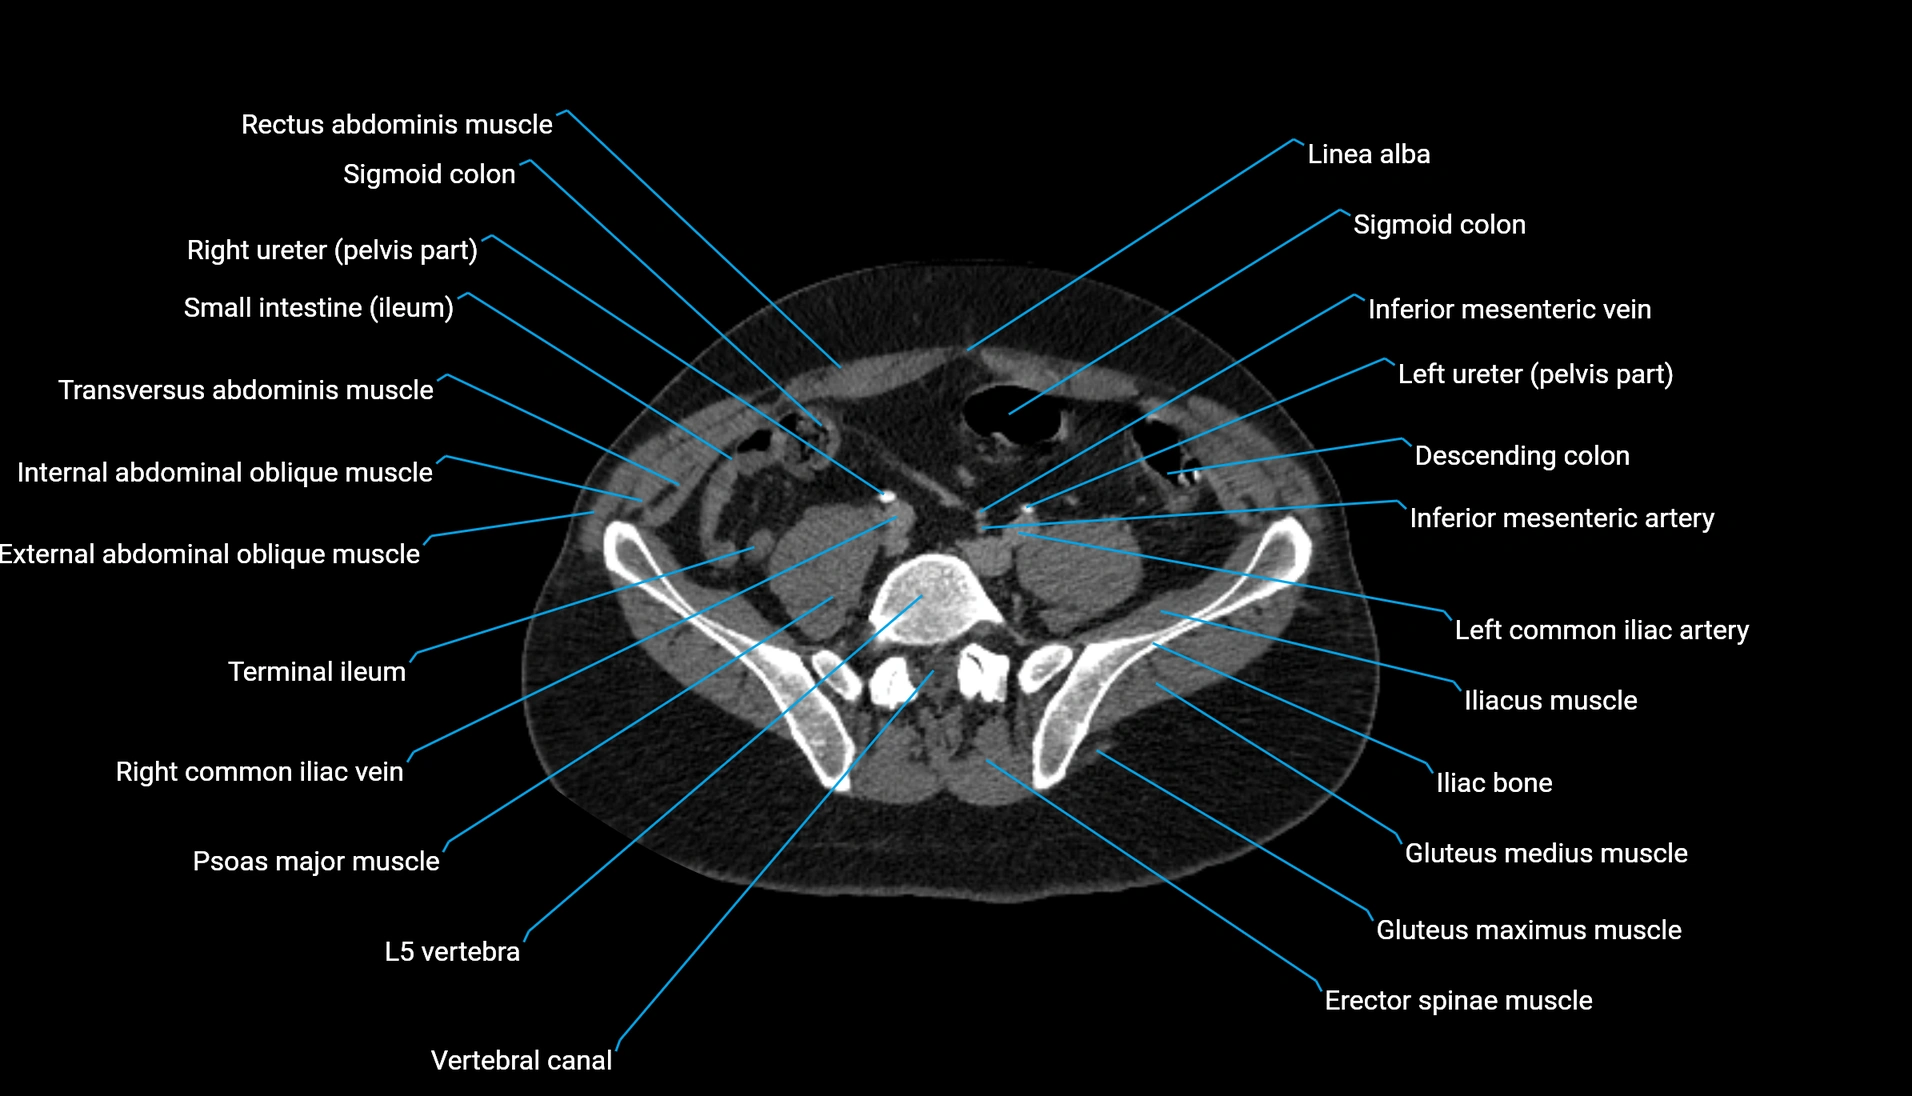

CT VRT 3D image

CT image